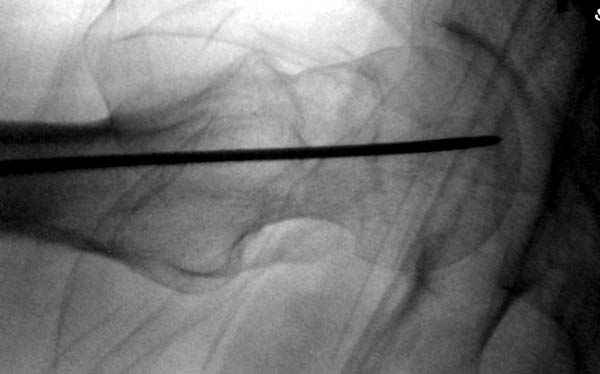

Правильно, ситуация изменилась, как говорят у нас теперь "different animal", надо решать проблему подвертельного перелома. При наличии различных вариантов фиксаторов, включая Страйкер Гамма 3, мы выбрали DePuy Antegrade Trachanteric Nail из-за многовариантности проксимальной фиксации и двойного изгиба. Вводится через вертел под 8 градусным углом, и есть достаточный передний диафизарный изгиб, предупреждающий пенетрацию дистального переднего кортекса.

Но ведь и головка бедра сползла в варус - отчего ограничились только фиксацией подвертельного перелома, а не убрали винты и не сделали репозицию шейки?